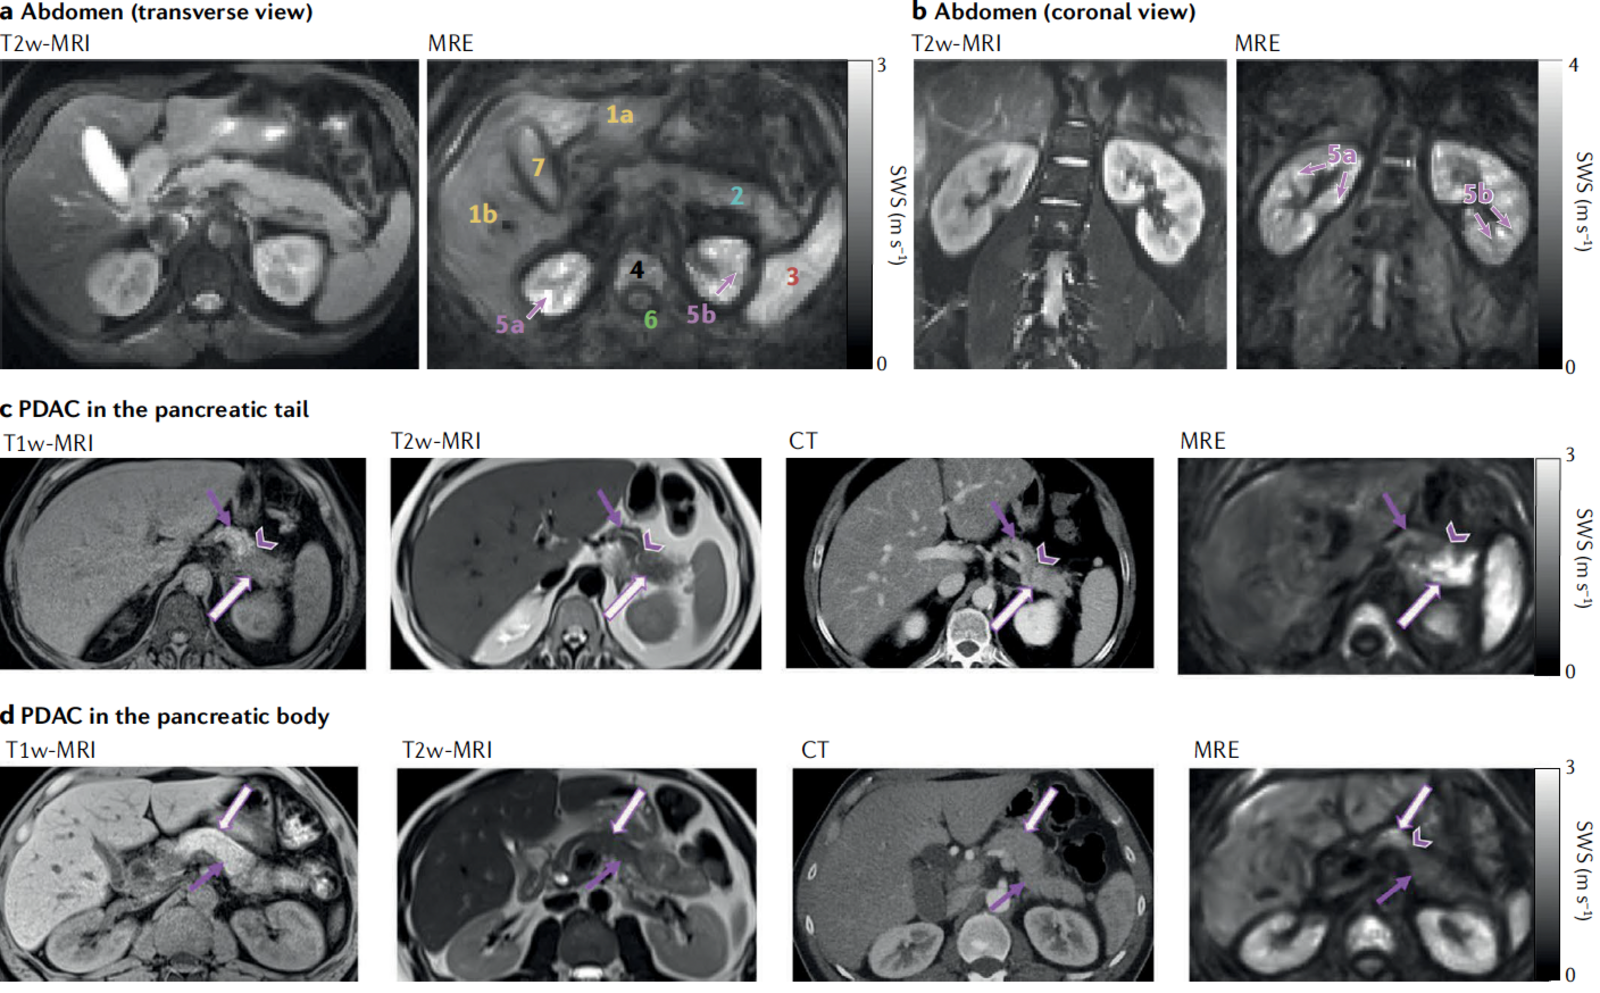

In addition, in a further sub-project, we explore the material properties of the brain in relation to neuroimaging in tumor patients, investigating the effects of degeneration, pressure, or stretching mechanisms on brain tissues and the resulting functional consequences, in terms of network and behavior. We use MR-Elastography (MRE) imaging to measure local physical properties of brain matter and add a novel material science perspective to the question of the brain's structure-function relationship.